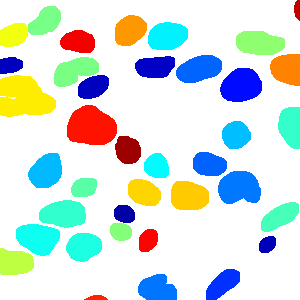

As an essential part of digital pathology, histopathology image analysis is playing increasingly important role in cancer diagnosis, which can provide direct and reliable evidence to diagnose the grade and type of cancer. This paper deals with nuclei segmentation, an important step in histopathological image analysis. The purpose of nuclei semgentation is not only counting the number of nuclei but also obtaining the detailed information of each nucleus. So unlike nuclei detection, here the outputs are the contour of each nucleus instead of only the position of their central points. Hence we can exactly extract each nucleus from the image and make it available for further analysis. For example, the features of the individual nucleus and the distribution of nuclei clusters can be used to grade and classify status of breast cancers [3, 4]. Because of appearance variation such as color, shape, and texture, nuclei segmentation from histopathological images could be very challenging, as illustrated in Fig.1, in which it is very challenging even for human to recognize and segment all nuclei within the images. Fig.1(a) and Fig.1(b) illustrate two histopathological images from different organs. Fig.1(c) and Fig.1(d) are two histopathological images from same organ but have different cancer grade.